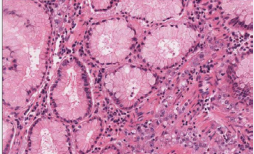

Histologically, the polypoid lesion was characterized by a proliferation of the surface foveolar cells lining exaggerated, elongated, and distorted pits that extend from the surface deep into the lamina propria with mucosal expansion. The glands developed extensive infoldings, branching in bizarre ways producing either a serrated appearance or dilated cysts, occasionally quite prominent. Smooth muscle fibers arborized in the lamina propria. Mucosa appeared edematous, infiltrated by single atypical discohesive epithelial elements, and characterized irregular and pleomorphic nuclei, eccentrically placed, with evident nucleolus, and ample eosinophilic cytoplasm and sporadically with classical signet-ring morphology. Plasma cells, lymphocytes and eosinophils were also present (Figure 4)

Figure 4: Hematoxylin-eosine staining.

Neutrophils were especially prominent in surface ulcerated areas; vascular proliferations resembling granulation tissue developed superficially near areas of inflammation. Within the foveolar hyperplastic lining there were areas of dysplastic changes as seen in the bioptic samples, with low and high grade intraepithelial neoplasia with features of signet ring cell (Figure 2-4)

Figure 2: Hematoxylin-eosine staining.

Figure 3: Hematoxylin-eosine staining